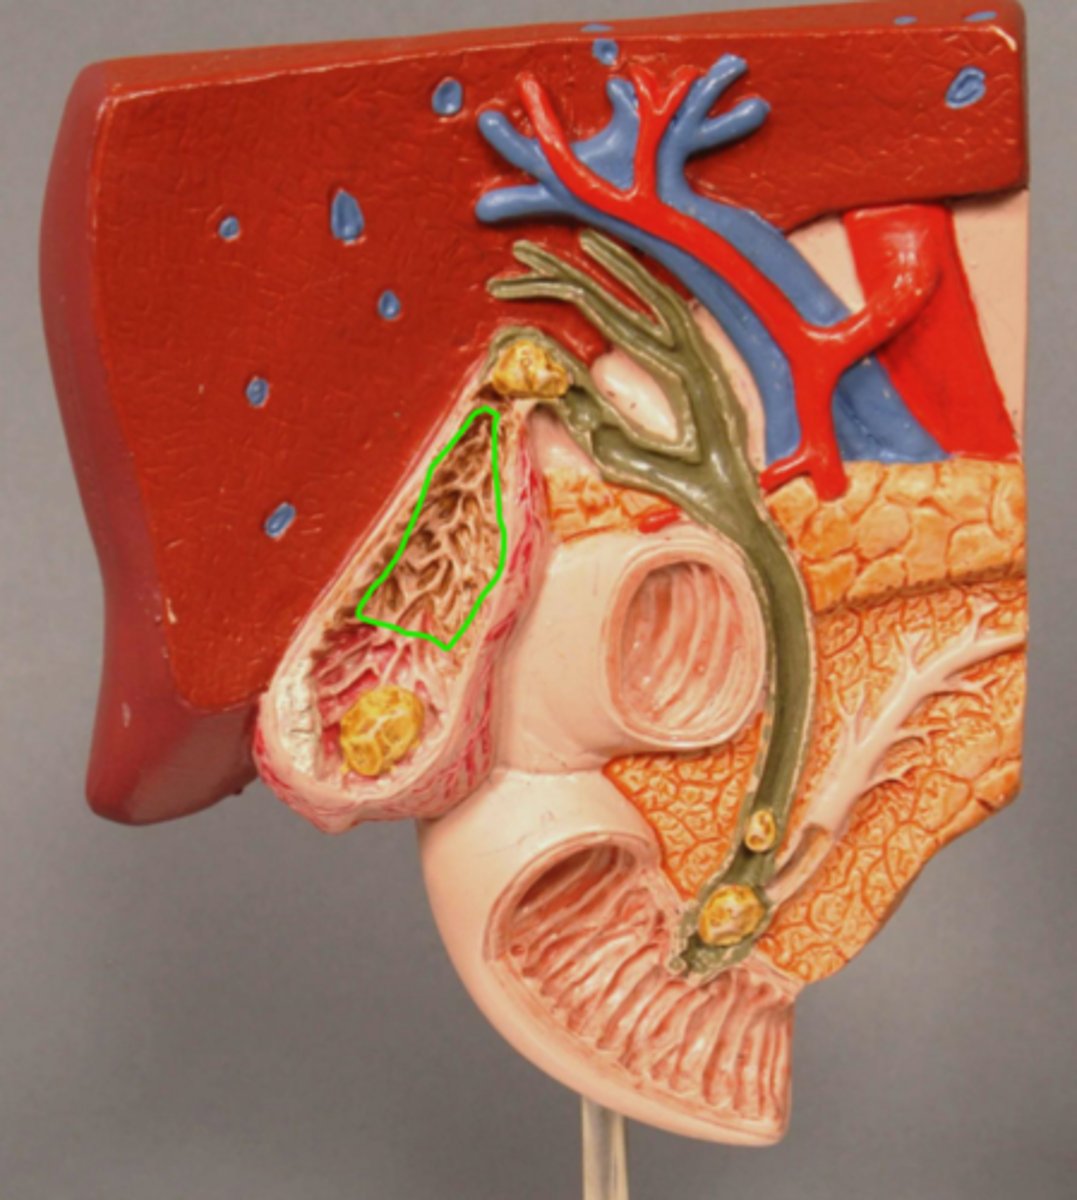

Acute Inflammation of Gallbladder (Cholecystitis)

Scarred wall of Gallbladder (Following Chronic Inflammation)